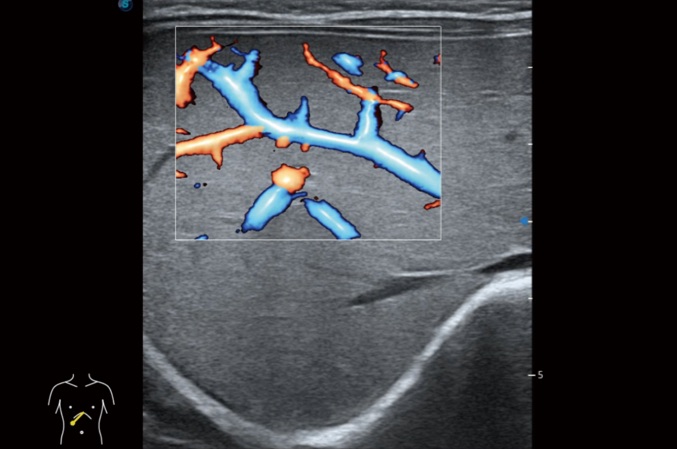

• Auto IMT

Auto IMT es una herramienta inteligente para analizar el riesgo potencial de enfermedad cardiovascular en un paciente. Al hacer clic en un botón, puede medir tanto el grosor de la íntima-media anterior como posterior de la carótida común. Este sencillo procedimiento mejora la productividad del examen, además de agregar valor de diagnóstico al examen.

Arteria carótida